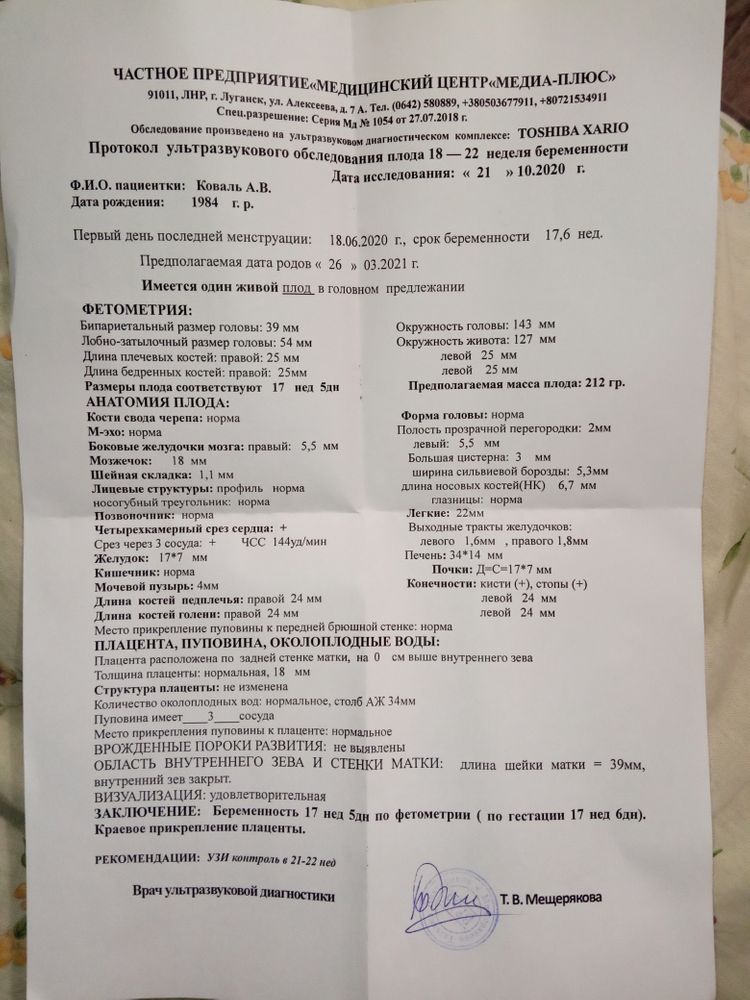

18 недель и 1 день) прошли мы второй скрининг, всё у нас как надо, по нормам. Вес 212 грамм) Муж был и старшая дочь, расплакалась) Днём была на рынке, подошла цыганка и говорит ты на нашу похожа, мальчика родишь, а я стою и офигеваю, как она заметила ,что я беременна 🤷 у меня широкое пальто, в нем вообще ничего не видно, плюс я стояла с пакетом у живота. Вечером на УЗИ, смотрит врач и говорит вооот смотрите половые губы, тоесть девочка, у меня первая мысль: вот циганка гадюка, соврала😂 немного бросило в жар, потому что уверена была в мальчике, а потом думаю ну и хорошо что дочь, имя то уже придумала классное- Мия♥️ начинает проходится по органам, всё хорошо говорит, а потом такая : о я вам наврала- вот же писюн! Мальчик у вас! И тычет папаше в писюн на мониторе 😂 короче сын у нас♥️